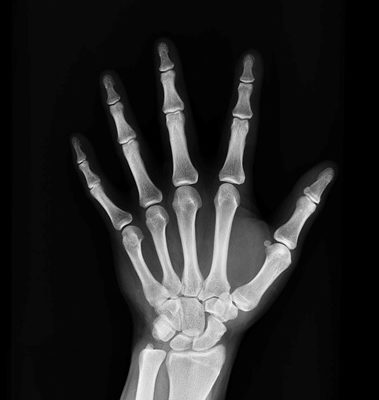

Рентген руки — это метод исследования костных структур на предмет переломов, трещин, остеопороза и других патологий. Рентгенологическое обследование — это современная и безопасная медицинская процедура.

Если есть подозрение на повреждение связочного аппарата, ушибы, переломы или растяжения, врач назначит рентген кисти. На полученном изображении хорошо видны патологические изменения. Сломанная рука проявляется рентгенологически полосой прозрачности, поврежденной надкостницей, приподнятыми краями и т. д.

Желательно регулярно делать фотографии руки, чтобы следить за процессами восстановления тканей. Эта процедура широко применяется в судебной медицине. Он определяет возраст пациента (костный возраст), определяет пол и профессию человека.